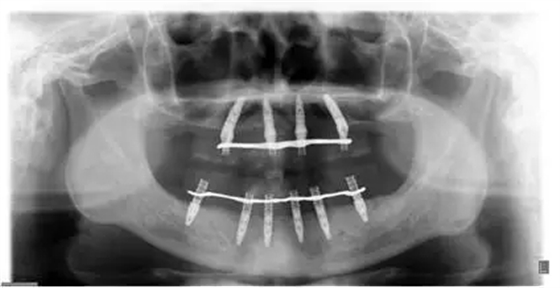

患者男性,51歲,全口無(wú)牙,下頜骨量尚可,上頜后牙區(qū)上頜竇底剩余骨高度嚴(yán)重不足,前牙區(qū)牙槽突較豐滿,主訴希望全口種植固定義齒修復(fù)。于2015年 9月接受種植治療:上頜采用All-on-4種植方案、下頜采用常規(guī)種植6顆種植體方案,種植后行即刻修復(fù)(圖1-2)。

10個(gè)月后出現(xiàn)左上頜咬合痛,X線檢查發(fā)現(xiàn)上頜左側(cè)前磨牙區(qū)傾斜種植體周圍低密度影,臨床檢查種植體松動(dòng),其余種植體骨結(jié)合良好,遂拔除該種植體(圖3-4)。愈合3個(gè)月,CBCT片顯示:25區(qū)種植窩空虛(圖5),愈合不佳,26區(qū)竇底剩余骨高度不足2mm(圖6),其余種植體骨愈合良好,15區(qū)傾斜種植體邊緣骨疑似吸收至第三螺紋(結(jié)合全景片)?;颊咭蠊潭ㄐ迯?fù)。